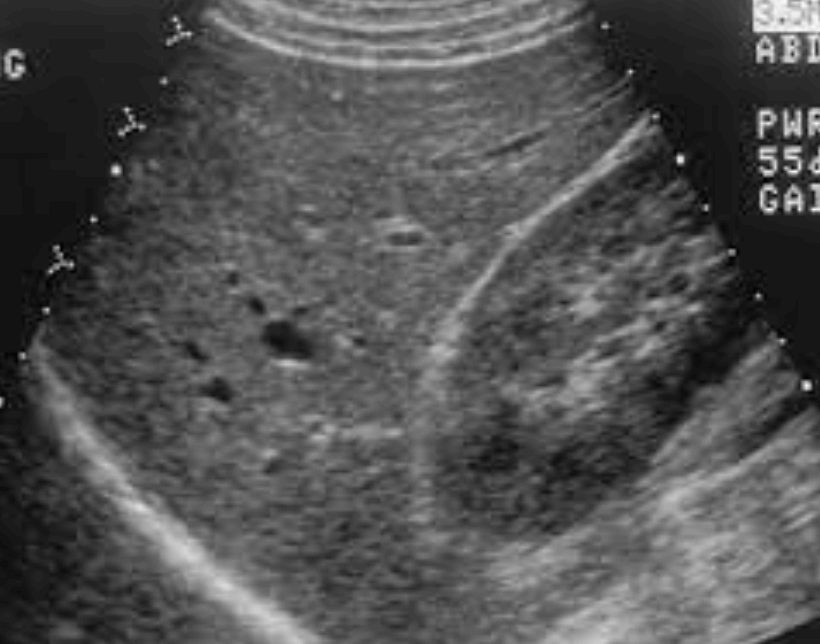

- 간실질의 불균질 한 에코가 증가한다.

- 문맥 말초지의 묘출 불명료

- 간의 변연이 둔탁해진다